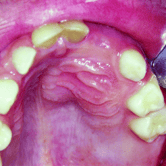

Dientes Supernumerarios

Los dientes supernumerarios son dientes adicionales que pueden aparecer en la boca y causar problemas de alineación o erupción de otros dientes.

Los pacientes pueden notar dientes adicionales en la boca, lo que puede causar apiñamiento o problemas estéticos.

El tratamiento incluye la extracción quirúrgica de los dientes supernumerarios.